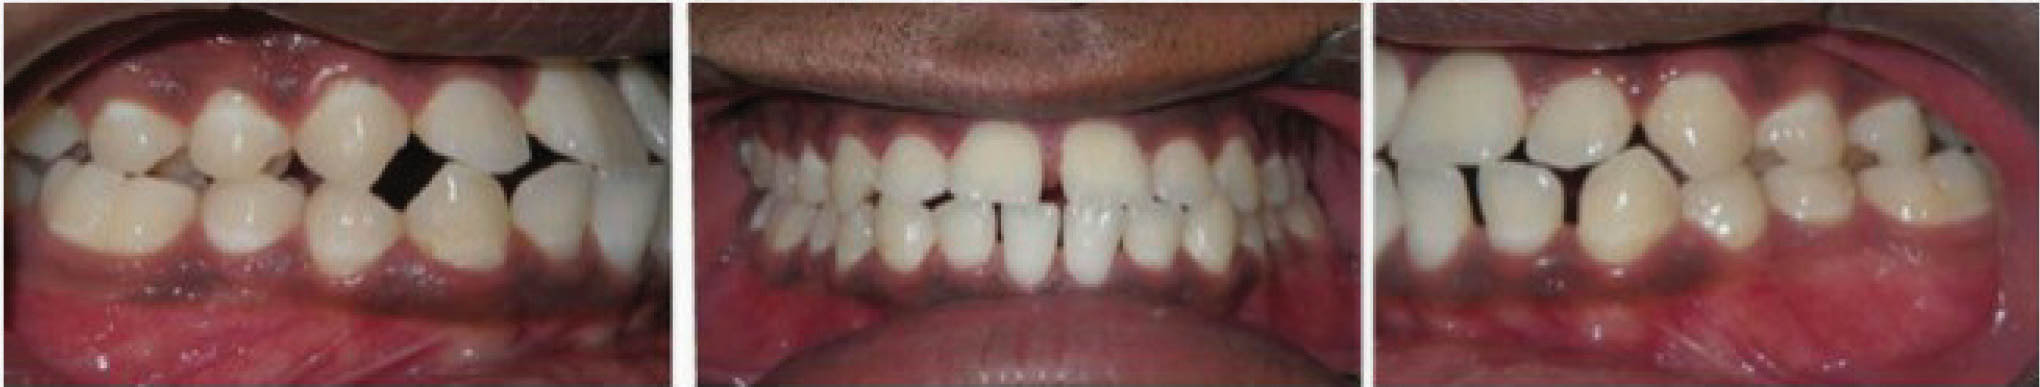

شکل 145-6 نحوه مرتب شدن دندانهای قدام پایین با 0.3mm استریپ هر کنتاکت را نشان میدهد. در پایان درمان قوس پایین کاملاً صاف شده است (شکل 146-6).

شکل 145-6